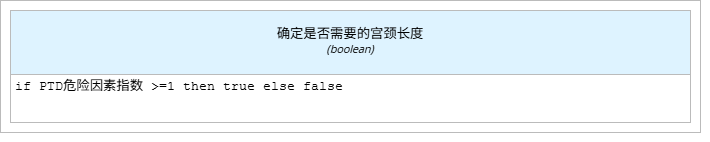

l “确定是否需要的宫颈长度”即根据“PTD危险因素指数”数字判断,使用文字表达式。